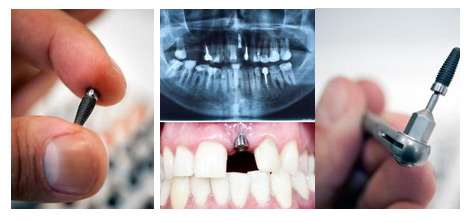

时隔半个世纪,种植牙已发生翻天覆地的变化。40年前,种植牙对患者的颌骨条件有着近乎苛刻的要求。而现在,拔牙后即刻种植、即刻修复、微创种植等使得不能种植的情况变少了。所以,从技术的进步而言,现在的患者,种植牙使用寿命理应大大超越40年前,维护得当可终身使用。

种植牙就像建房子打地基,对医生的技术和经验有着极高的要求,因为牙槽骨很小,要根据患者的牙槽骨条件,在保证不损伤神经、不种到骨头外面的前提下,还要准确控制钻孔时的方向、深度、转速,植入尽可能长、尽可能粗壮的种植体,如果是多颗或者全口种植牙,还要考验牙医对力学的掌握程度,能合理设计植入位置和数量,才能保证种植牙的长期效果。

就目前来说,种植牙系统有很多,目前比较流行的属欧美和韩国种植系统,而不同的种植牙系统,外形设计和表面处理技术存有较大差异,导致骨结合的速度和质量存在差异,耐用程度也会有差异。所以种植系统并非越贵越好,只有适合自己的才是较 好的。